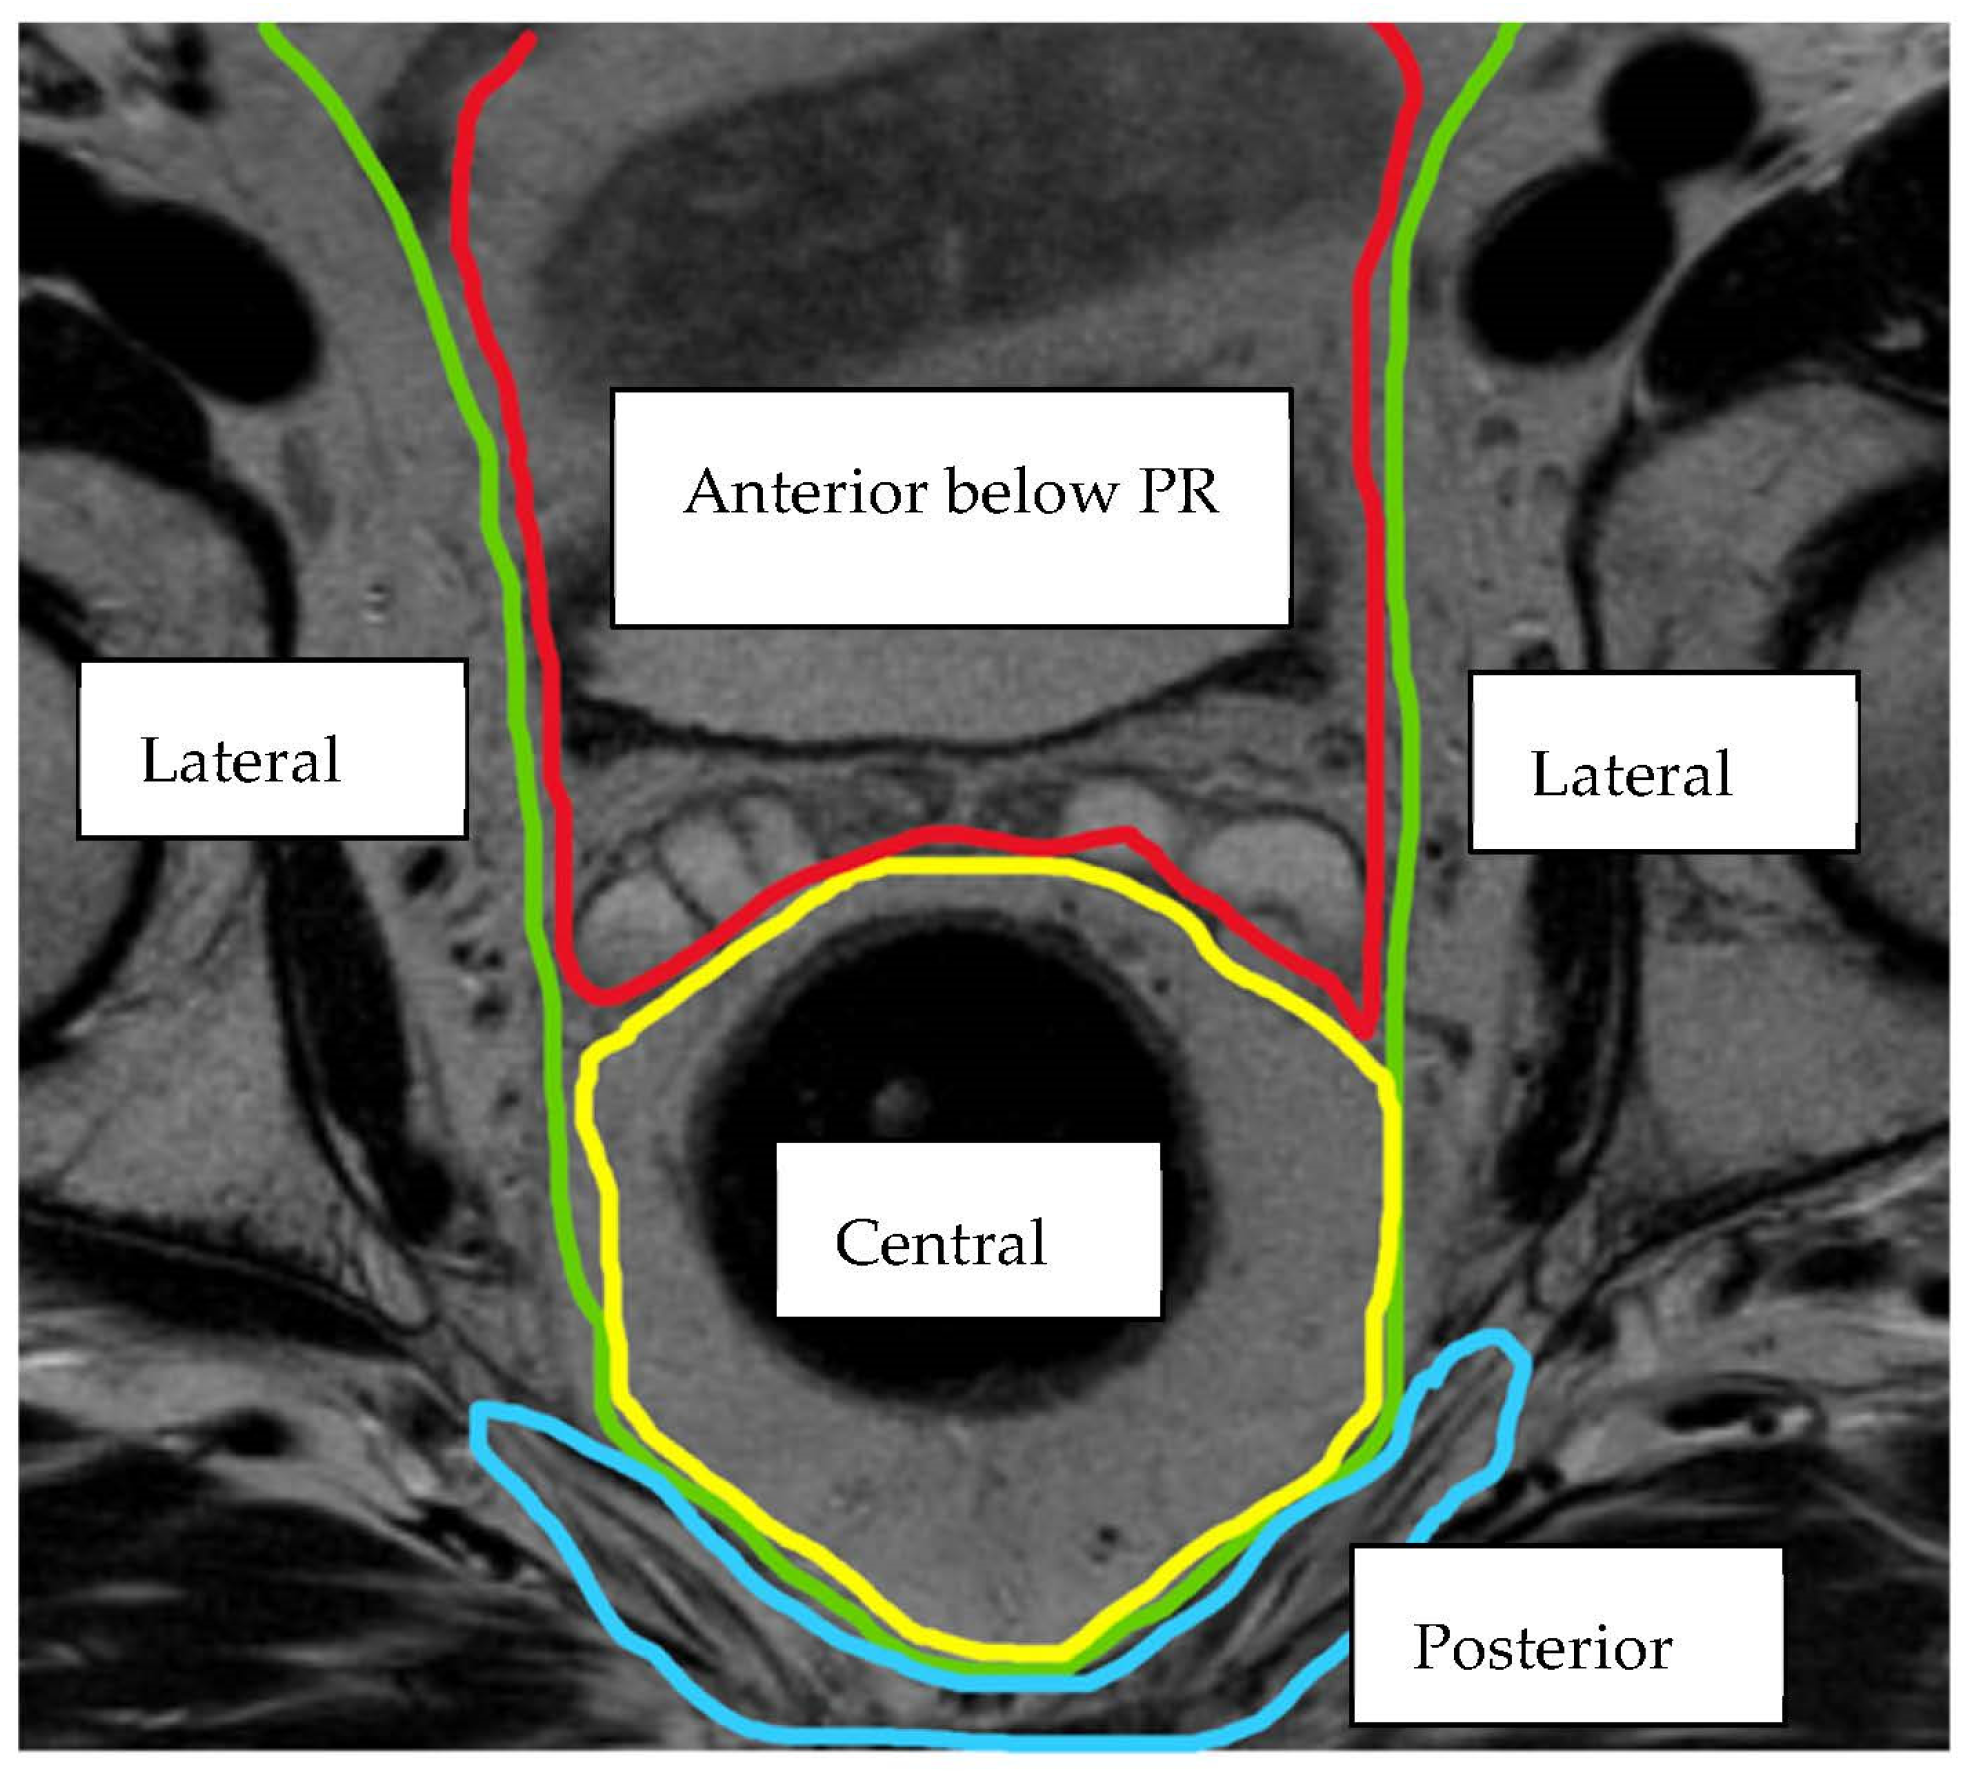

| Compartment | Structures within Compartment |

|---|---|

| Anterior above Peritoneal Reflection | Ureters, iliac vessels above peritoneal reflection, sigmoid colon, small bowel, lateral pelvic sidewall fascia (peritoneal surface) |

| Anterior below Peritoneal Reflection | Genitourinary system (seminal vesicles, prostate, uterus, vagina, ovaries, bladder/vesico-ureteric junction, proximal urethra), pubic symphysis |

| Central | Rectum/neo-rectum (intra/extra-luminal), perirectal fat or mesorectal recurrence |

| Posterior | Coccyx, pre-sacral fascia, retro-sacral space, sacrum, sciatic nerve, sciatic notch, S1 and S2 nerve roots |

| Lateral | Internal and external iliac vessels, lateral pelvic lymph nodes, piriformis muscle, internal obturator muscle |

| Infralevator | Levator ani muscles, external sphincter complex, ischio-anal fossa |

| Anterior Urogenital triangle | Perineal body/perineal scar (if previous abdomino-perineal resection of rectum), vaginal introitus, distal urethra, crus penis |